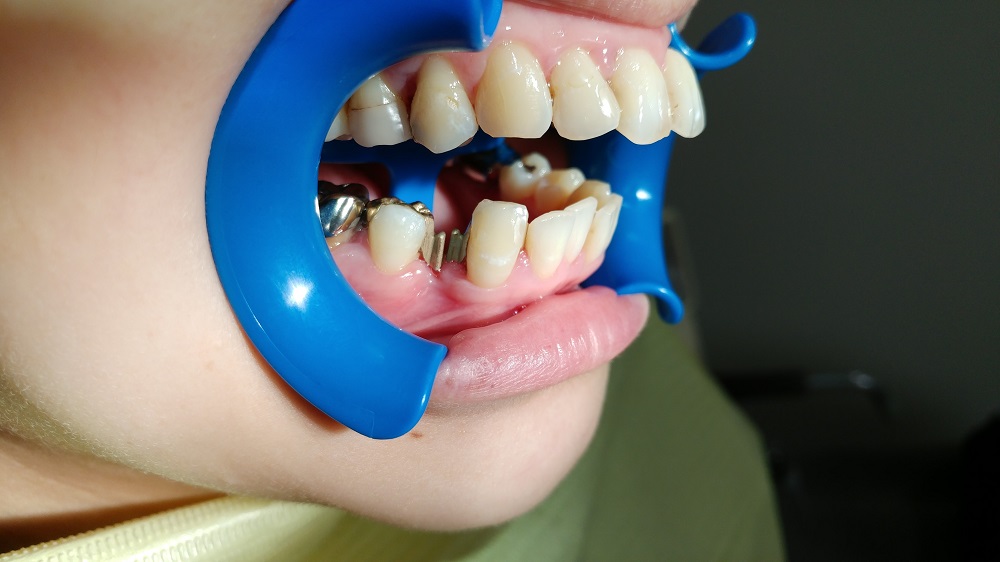

3つのパーツから出来上がっており

この場合は犬歯から

ついで奥のインレー 見てお分かりだろうが、金属のフックのようなものがある

ここにダミーの歯をセットする

外側から見ると犬歯は天然のまま手つかずの状態に見える

奥歯も詰め物でなければそうなるし、白い詰め物をして、その上からも可能である

審美的にも優れている